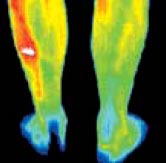

What is Thermography?Thermography, or Digital Infrared Thermal Imaging (DITI) is a noninvasive diagnostic technique that allows the examiner to visualise and quantify changes in skin surface temperature.

The spectrum of colours indicate an increase or decrease in the amount of infrared radiation being emitted from the body surface. Since there is a high degree of thermal symmetry in the normal body, subtle abnormal temperature asymmetry's can be easily identified. Medical DITI's major clinical value is in its high sensitivity to pathology in the vascular, muscular, neural and skeletal systems and as such can contribute to the pathogenesis and diagnosis made by the clinician. |

An infrared scanning device

is used to convert infrared radiation emitted from the skin surface into

electrical impulses that are visualised in colour on a monitor. This

visual image graphically maps the body temperature and is referred to

as a thermogram.